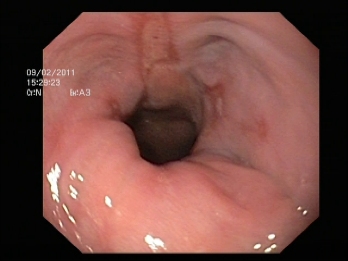

- Endoscopia digestiva alta (o esofago-gastroscopia): Permite confirmar la presencia de una hernia de hiato y en caso de que exista reflujo gastroesofágico evidenciar la presencia de esofagitis si la hubiera. Permite tomar biopsias para descartar lesiones premalignas en el esófago de Barret.